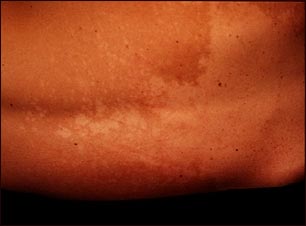

Tiña versicolor en la espalda

El organismo Pityrosporum ovale causa la tiña versicolor, condición que suele presentarse más a menudo en los adultos jóvenes. Si se la examina bajo la lámpara de Wood se ve una fluorescencia de color amarillo verdoso pálido; si se la examina con un preparado de hidróxido de potasio se ve la apariencia típica de "espagueti con albóndigas", con hifas y esporas. Las lesiones cutáneas son máculas con bordes muy pronunciados, ya sea hiper o hipopigmentadas, recubiertas de finas escamas. Las lesiones pequeñas y discretas con el tiempo pueden fundirse para cubrir áreas extensas del tronco.